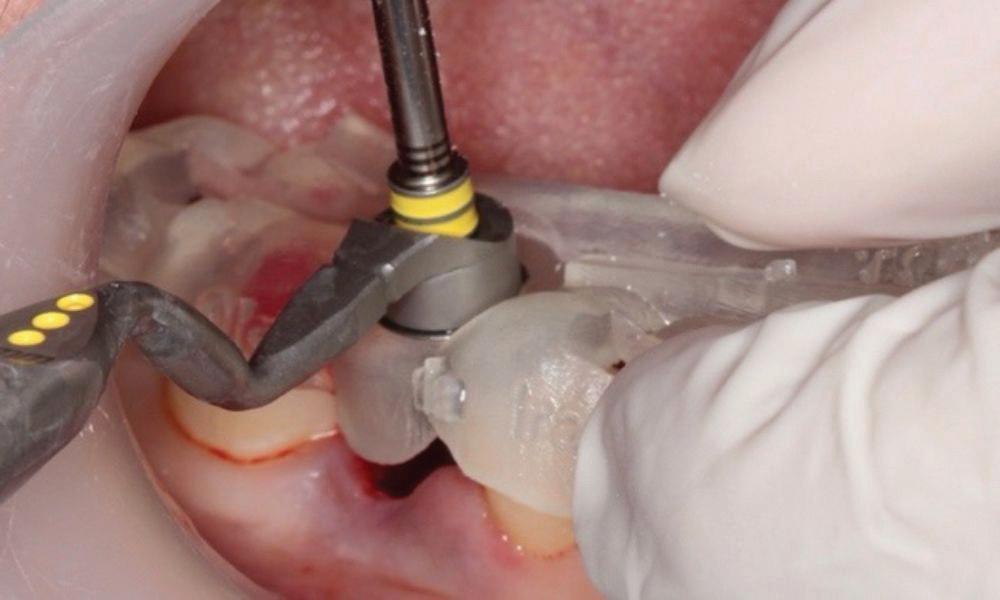

With the increasing use of all ceramics within practice, a clinician must under stand adhesive procedures to ensure adequate bond strength for predictability and longevity. Clearfil ceramic primer plus is a single com ponent adhesive primer used to enhance bond strength between resin-based materials, as well as porcelain, composite, hybrid ceramics, metal oxide (zirconia) and lithium disilicate. It contains the adhesive phosphate containing monomer (MDP) used for adhesive bonding as well as to metal oxide. Additionally, it contains a silane cou pling agent which guarantees strong adhesion to all glass-based ceramic materials. It is a one bottle system meaning there is no mixing and has excellent shelf life compared to other silanes which need to have careful storage.

Estelite Asteria (Tokuyama)One of my favourite composite resin materials is Asteria which is a light-cured radiopaque composite for universal use. It considerably simplifies multilayer techniques yet delivers outstanding aesthetics with excellent polishability. Unlike mul tilayer techniques used with conventional composites, Asteria uses only 2 layers for optimal results without compromising aesthetics. The microstructure of the material produces a light diffusion that helps blend in with the natural tooth structure. The chameleon like nature of the material allows a blending of the materials to natural tooth structure and it allows excellent polishability which retains its lustre over time.